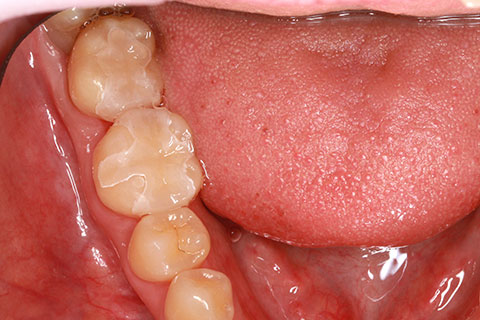

• オールセラミックの症例1

治療前

治療後

上顎前歯のデコボコと色調を改善。

年齢・性別

40歳女性

治療期間

1ヶ月

抜歯

なし

治療費

35.2万円

備考

前歯4本の変色歯及び歯列不正によるセラミック治療

治療内容

歯質を削除し、セラミック冠をセメント合着

施術の副作用(リスク)

知覚過敏、歯髄炎、荷重負担